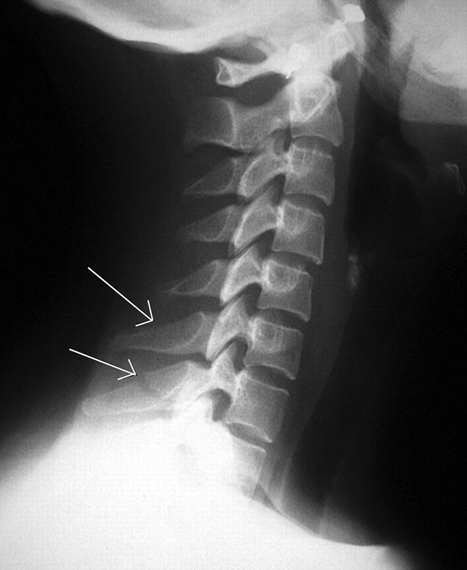

(2)Clay shoveler骨折

下颈椎或上胸椎棘突骨折。1940年德国Hall等报道13例棘突骨折的患者,这些患者均为铲土工人,因此Hall将这类孤立性的棘突骨折命名为Clay shoveler骨折,即“铲土者骨折”。